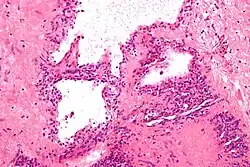

Micrograph showing a pancreatic serous cystadenoma, a type of cystadenoma. H&E stain.